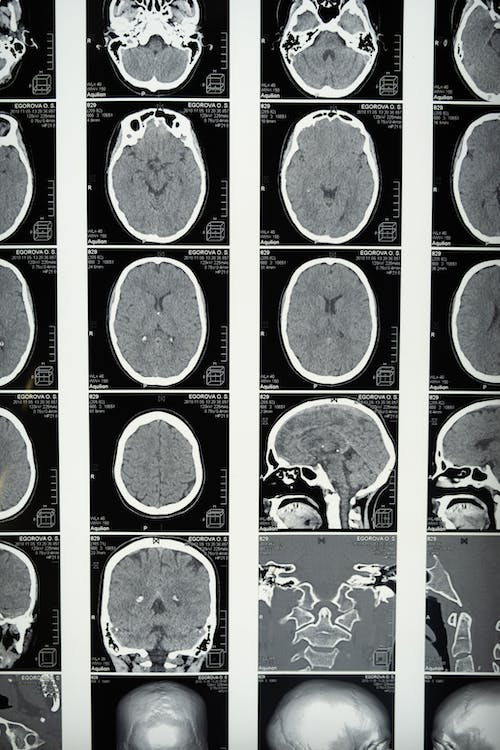

Cuando la corteza visual se daña

Los trastornos de la corteza visual pueden manifestarse de diferentes maneras, incluyendo dificultades para reconocer caras, trastornos en la percepción de los colores y problemas con la percepción del movimiento. Tales dificultades pueden tener diversas causas, que van desde lesiones cerebrales traumáticas y derrames cerebrales hasta trastornos genéticos y enfermedades neurodegenerativas.

Aquí, diversos factores pueden incidir. Entre ellos se encuentra la edad, estilos de vida poco saludables y antecedentes familiares también pueden influir en el desarrollo de tales afecciones (Álvarez y Masjuan, 2016).